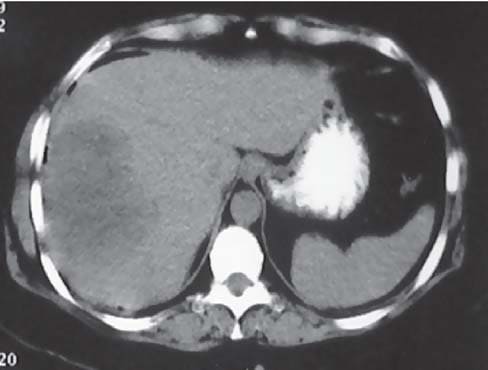

3) инструментальные методы исследования (УЗИ, МРТ, КТ, рентгенография);

Альвеококкоз, узел на КТ